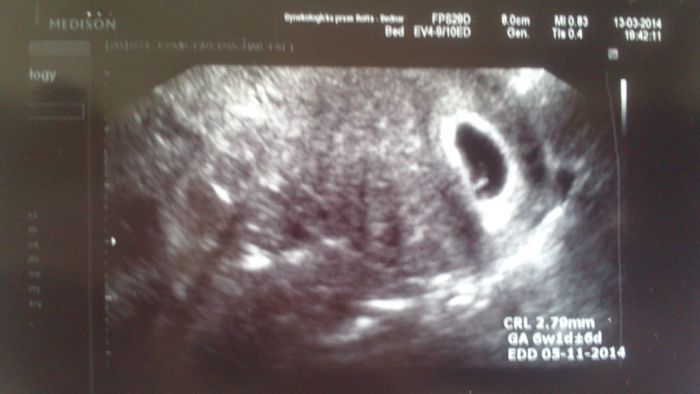

Ahoj, tak snad se mi konečně podařilo fotku přetáhnout a vložit

Každopádně mám pocit, že v reálu jsem i já (!) viděla na obrazovce víc, než je na tom snímku..... No, ale přikládám.

Sari-Mari - jéé fazolka :) krasnaaaa

Nj, škoda že tam není vidět aspoň ten stín váčku :) ale to nevadí, viděla jsem i blikat srdíčko a to je nejdůležitější :) Těším se moc na vaše fotečky!